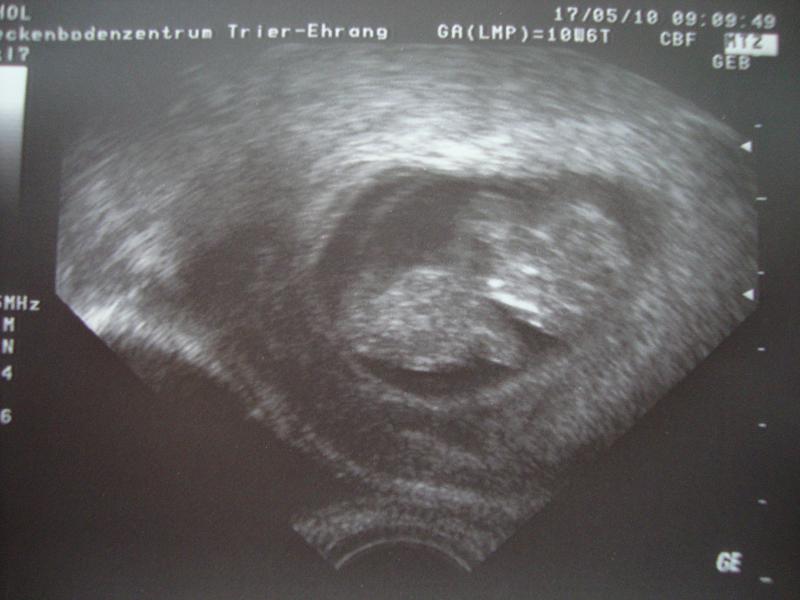

Es war ein riesiges Hämatom und die Gefahr war ziemlich groß dass entweder das Baby mit abblutet oder die Versorgung abgedrückt würde, weils direkt an der FH war, aber Hanni hat es zum Glück gut überstaden, wächst und gedeiht prächtig. Hoffe es bleibt jetzt so und ich kann einfach ganz normal schwanger sein. Nächsten Mittwoch hab ich wieder Termin bei meinem FA. Ich häng noch das neueste US-Foto an.

Dateianhänge

US Bild 20.05.2010 004kl.jpg